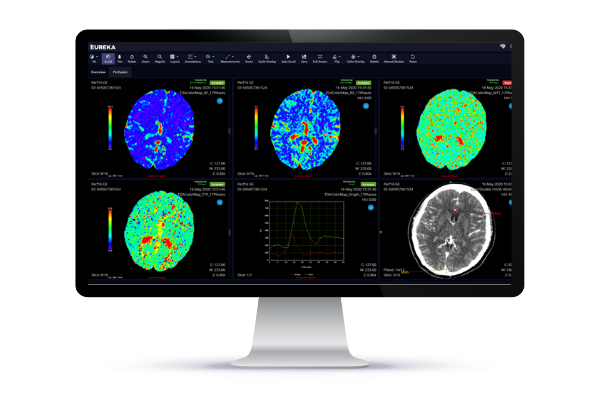

November 27, 2023 — ConcertAI's TeraRecon, the advanced visualization and clinical AI leader, recently unveiled first-in-category capabilities in advanced visualization, AI, and expansions to its AI partner ecosystem to enhance research capabilities and support complex clinical study workflows. These solutions will provide researchers with enhanced data analysis tools for in-depth study, contributing to more informed care strategies that can improve patient outcomes.

At this year's RSNA 2023, ConcertAI, and its TeraRecon clinical imaging solutions group, are formally launching a multi-modal AI platform aligning clinical, radiological, whole slide images/digital pathology, along with real-world patient data in support of AI model development for clinical research, clinical trials, and deployment of AI models for prospective clinical validation.

As part of this announcement, ConcertAI is engaging in a multi-year strategic agreement with Memorial Sloan Kettering Cancer Center (MSKCC) focused on advancing Clinical AI in oncology, with an emphasis on enhancing clinical trials and improving oncology decision-making. Leveraging ConcertAI's Eureka Life Science AI Platform, powered by TeraRecon, MSKCC will drive advancements in multi-modal AI workflows, using clinical and radiological imaging data. This collaboration aims to use advanced data analysis and AI methods to predict specific tumor mutations and cancer treatment response, contributing to the broader field of oncology research. Our joint vision is clear: advance the utility and efficacy of Clinical AI in oncology research, extending its benefits to more patients and institutions in the future.

ConcertAI’s TeraRecon will also be showcasing new and expanded collaborations within the Eureka Clinical AI Partner Program, including: Avicenna.AI, Bot Image, Cercare Medical, Coreline Soft, GLEAMER, Infervision, Lucida Medical, Optellum, Riverain, and Us2.ai, adding to its large catalog of AI models, offering solutions that enable clinicians to efficiently interact with AI findings, in one streamlined place by integrating seamlessly to PACS or Advanced Visualization solutions.

ConcertAI’s TeraRecon is also announcing the launch of Pulmonology Suite, a collection of the leading, vendor-neutral, Pulmonology AI algorithms that aid in the analysis and interpretation of Chest CT scans to assess, monitor, and provide insights to support clinicians in treatment decisions for pulmonary conditions. Possible applications of Pulmonology Suite are to aid physicians including pneumothorax, lung nodules, and incidental pulmonary embolism. Pulmonology Suite complements Neurology Suite and Cardiology Suite, released earlier this year.